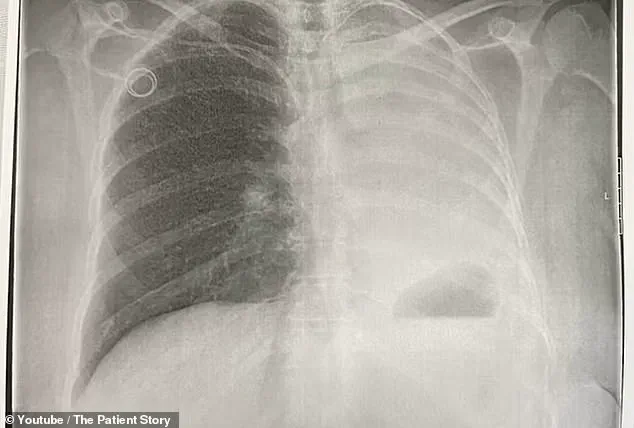

By the time her condition was fully mapped out, the cancer had metastasized from her uterus to her lung—a development that would forever alter the trajectory of her life.